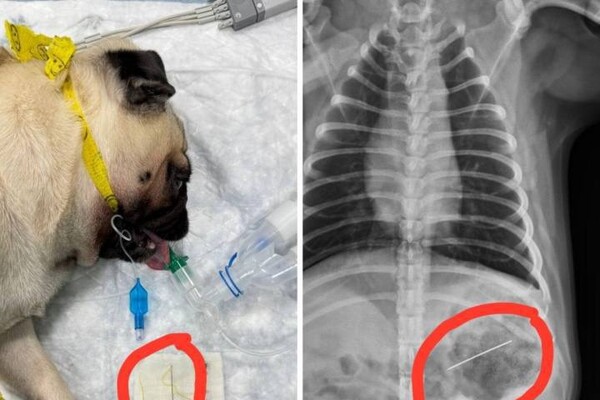

Инцидент произошел с мопсом по кличке Джамбо. Во время игры пес проглотил иголку, после чего хозяева сразу отвезли животное в ветеринарную клинику.

Хирурги клиники провели собаке операцию. Они смогли вытащить иголку из организма мопса с помощью эндоскопа.